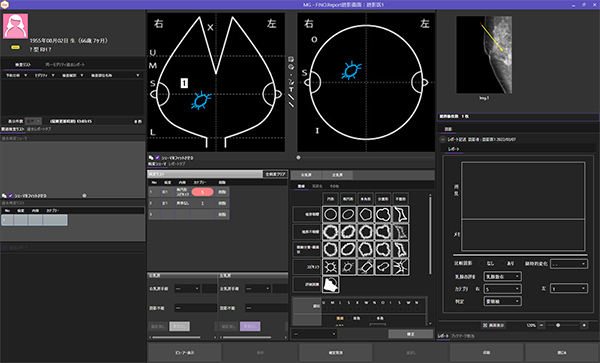

特長<2>

乳腺領域に特化した充実機能

トモシンセシスやCAD表示などの乳腺領域特有な表示に対応可能です。また,マルチモダリティ対応で乳腺に関するMRIやUS画像を同一ビューワー上に表示が可能です。

特長<3>

多彩な機能で乳腺領域のレポート作成を幅広く支援(オプション)

マンモグラフィガイドライン第4版に準拠し,病変アイコンの貼付によりカテゴリーを自動反映可能です。複数読影の対応により様々なステータスでの管理が容易で,乳房超音波検査との総合判定機能にも対応します。乳腺領域だけでなく,放射線,内視鏡,生理検査等を含めた統合レポートとしても使用できます。